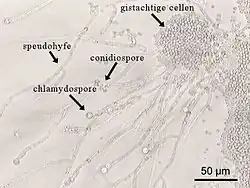

- 'chlamydosporen' zijn ongeslachtelijke rustsporen van gisten. Deze dikwandige sporen kunnen ongunstige omstandigheden, zoals droge of hete seizoenen, overleven. Chlamydosporen hebben een ronde vorm en een glad oppervlak. Ze zijn meercellig, waarbij de cellen via poriën in het septum met elkaar in verbinding staan.

Chlamydospore van de gist Candida albicans

Chlamydospore van de gist Candida albicans